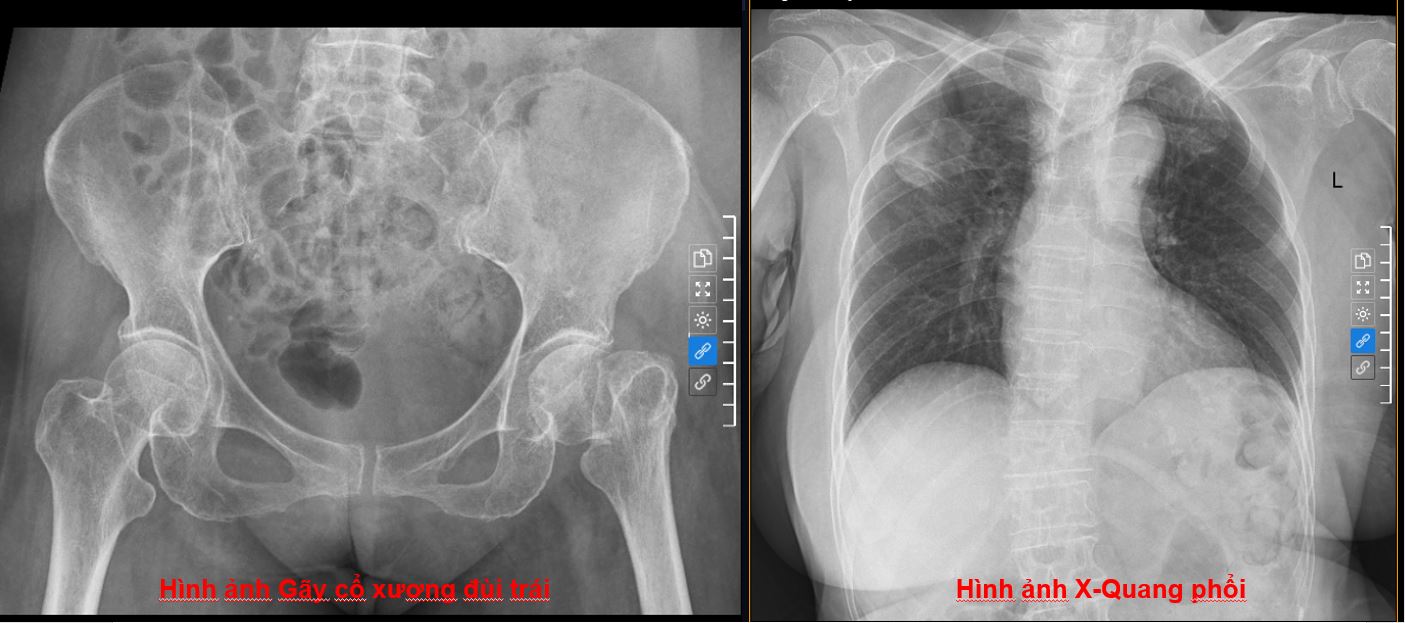

Hình ảnh phim chụp X-Quang gãy cổ xương đùi trái và chụp X-Quang phổi của bệnh nhân.